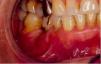

El absceso periodontal aparece cuando existe una bolsa periodontal profunda con exudado inflamatorio y se obstruye la vía natural de drenaje, acumulándose en su interior el contenido inflamatorio (fig. 2).

Fig. 2. En la imagen se aprecia un absceso periodontal localizado en la encía vestibular correspondiente al canino inferior derecho (portador de una corona de oro), con bolsas periodontales profundas.